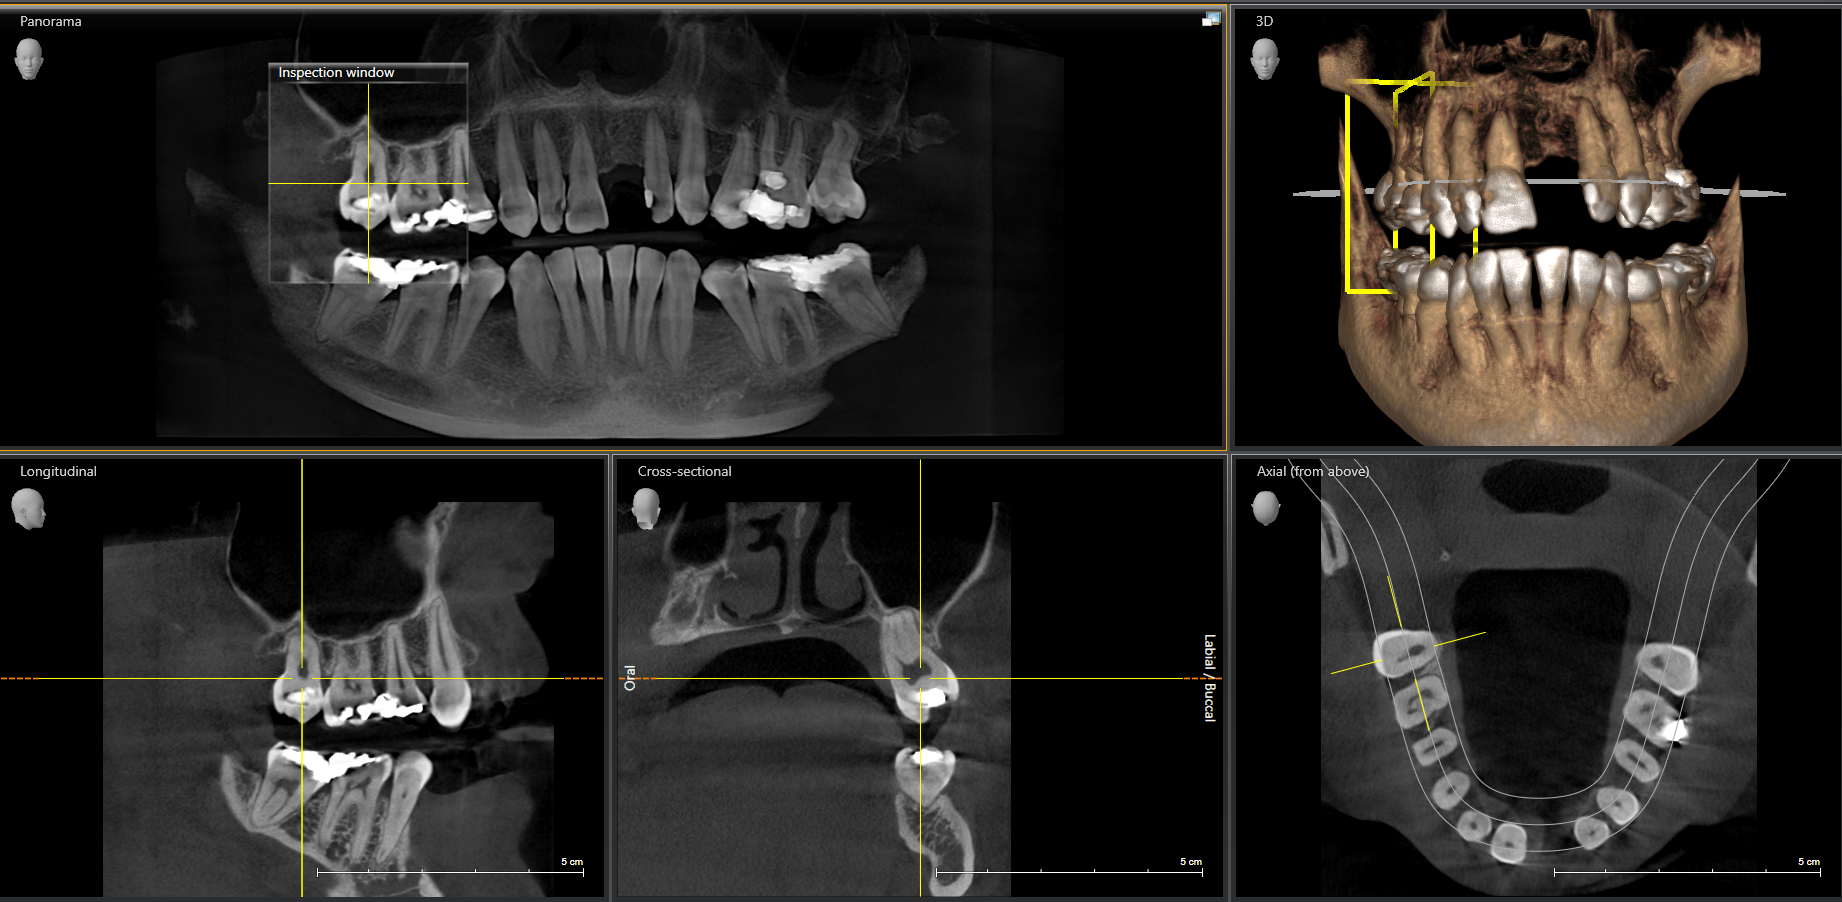

We start with a comprehensive full mouth examination, digital X-rays, a dental 3D(CBCT) scan and Trios5 Scan. The scanned images provide high-resolution images in a three dimensional plane. We use these images and scans for precise treatment planning.

CBCT 3D Scan

Using the 3D images in special planning software, the Dentist maps out the exact position and angle of insertion of each implant. They take care to place implants where they will be stable and in the best position to support the replacement teeth. They will also plan out any bone grafting (if needed) to ensure the implants have strong bone support.